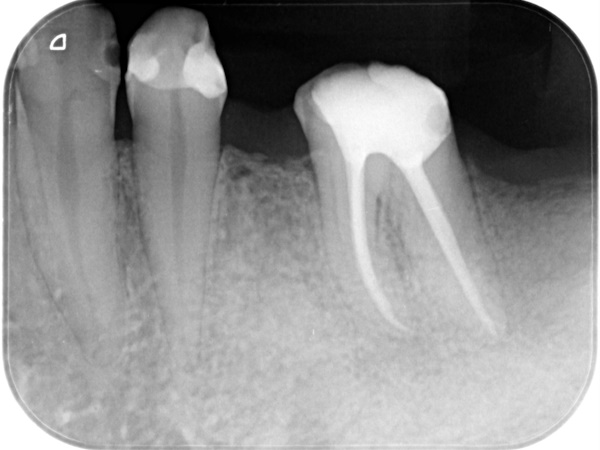

治療前と治療後の比較

術前から術後までの治療の流れ

初診時

根管治療終了後3か月経過